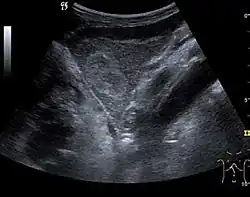

Hepatic hemangioma (2D). The lesion is located in the left hepatic lobe. Note precise delineation, their increased echogenity and the heterogeneous internal structure.